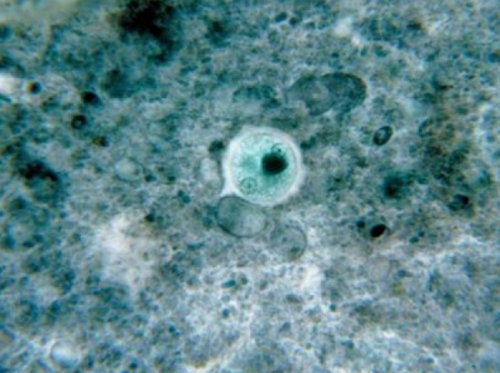

少年感染食腦蟲死亡,圖為阿米巴原食腦蟲

食腦蟲又稱“吃腦寄生蟲”,會(huì)引發(fā)阿米巴痢疾、肝膿腫、腦膜腦炎、角膜炎、口腔感染和皮膚損傷等。人在江河湖塘中游泳或用疫水洗鼻時(shí),食腦蟲會(huì)進(jìn)入鼻腔,其后上行入腦,侵入中樞神經(jīng)系統(tǒng)。對(duì)人體的危害性十分大。

報(bào)道指出,這種聽上去駭人萬分的“食腦蟲”雖然只是單細(xì)胞生物,但卻能通過鼻孔進(jìn)入中樞神經(jīng)系統(tǒng),感染大腦,最終導(dǎo)致被感染者腦死亡。雖然在過去53年內(nèi)只有133起“食腦蟲”感染記錄在案,但一旦感染,這種病菌非常致命,此前僅有3人在感染“食腦蟲”后存活下來。